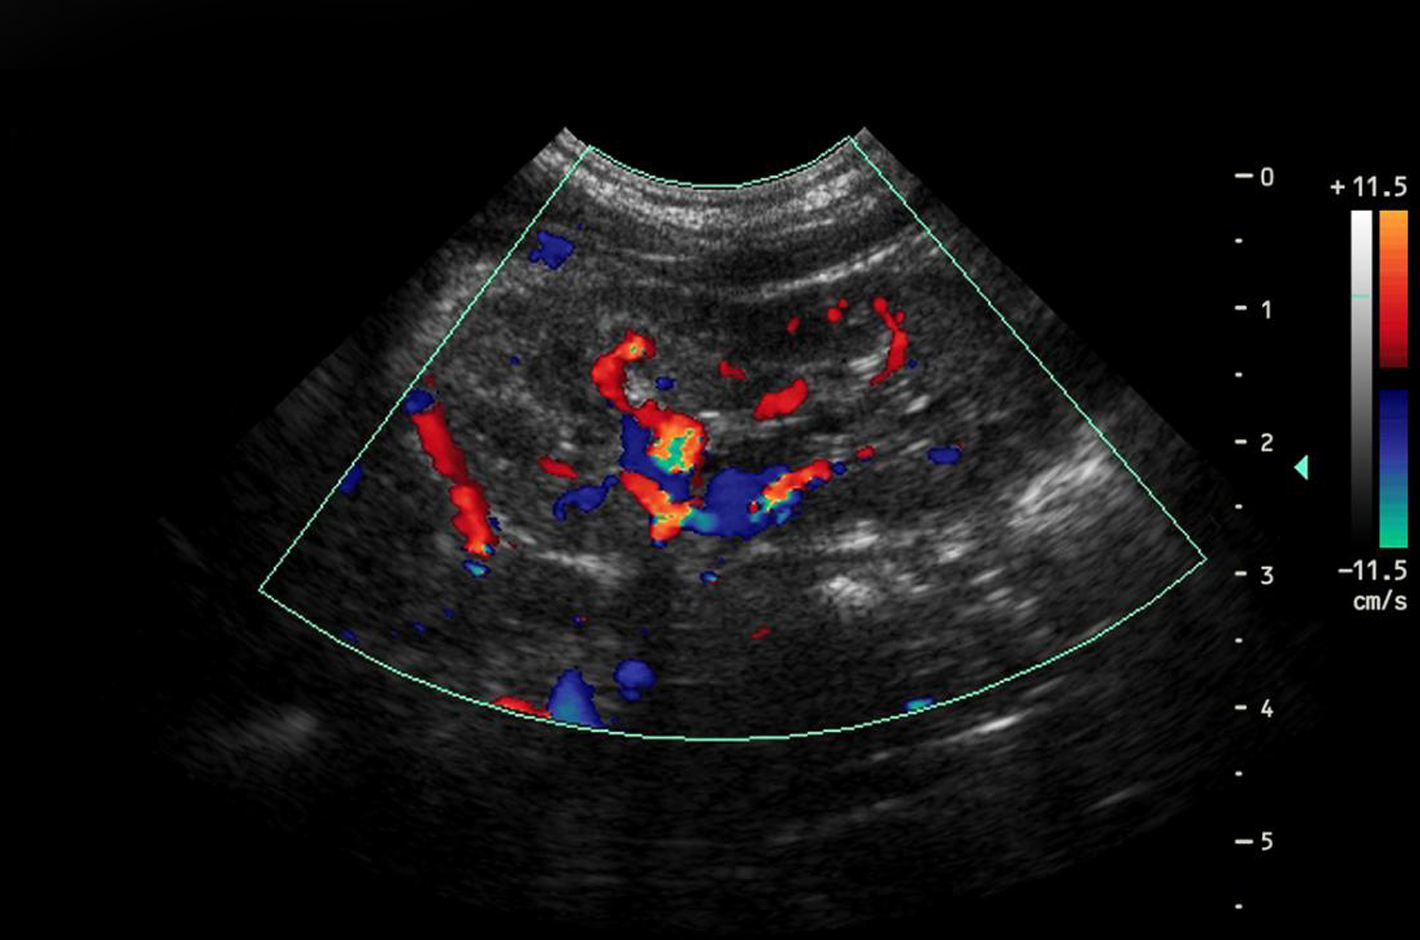

L’Eco Color Doppler è una tecnica di ecografia non invasiva che combina le immagini tradizionali dell’ecografia con una valutazione del flusso sanguigno attraverso i vasi sanguigni. Questo permette ai medici di vedere in tempo reale come il sangue fluisce attraverso arterie e vene, identificando aree di turbolenza o riduzione del flusso che possono indicare problemi vascolari. È spesso utilizzato per esaminare le condizioni delle arterie carotidi, le vene degli arti superiori e inferiori e altre parti del corpo.

Questo tipo di ecografia Doppler a colori è fondamentale per valutare la salute delle arterie e delle vene, permettendo di individuare eventuali ostruzioni, coaguli o anomalie nel flusso sanguigno.